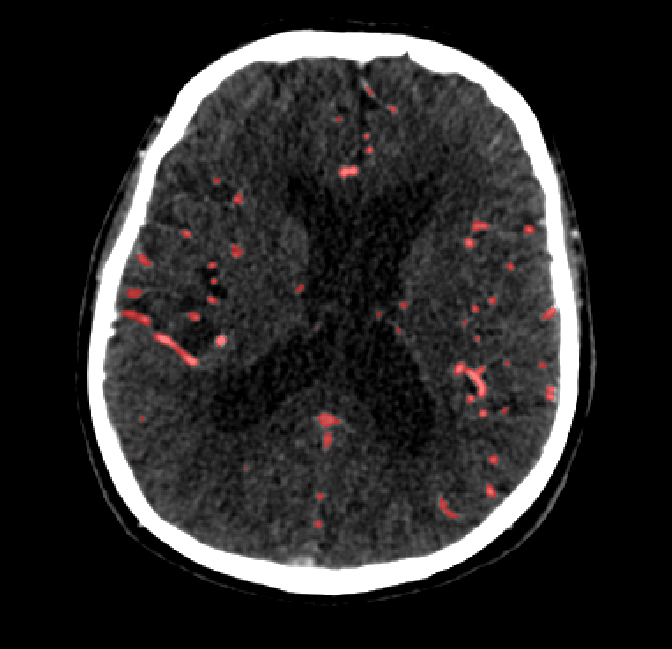

After fine-tuning, the two pre-train conditions appear to have little or no difference in terms of qualitative performance at the vessel segmentation task. However, when compared to the models trained only on real data, there are noticeable differences. Throughout Figures 4.3-4.9, the model pre-trained on scans with original CT noise is to be taken as representative of segmentation performed by the Perlin noise pre-training condition. Images showing the hand-labeled ground truth, as well as the unlabeled slice, are presented for comparison.

Figure 4.5: Segmentations on a central slice. Unaltered image (left). No pretrain model (mid-left). Fine-tuned model (mid-right). Hand-labeled ground truth (right).

Refer to caption

Figure 4.6: Segmentations on a central slice. Unaltered image (left). No pretrain model (mid-left). Fine-tuned model (mid-right). Hand-labeled ground truth (right).

For vessels in the center of the head, all model types appear to accurately segment vessels. In certain cases, the models appear to learn to correctly avoid segmenting pieces of bone that could, in terms of shape and contrast, easily be confused with large vessels. An example of this can be seen in the frontal section of Figure 4.6.

The models appear to have a hard time segmenting vessels close to the skull surface. The model trained exclusively on patient data appears to struggle far more for these types on conditions than the fine-tuned models. Figure 4.8 shows an example of the fine-tuneds model having close to no trouble segmenting vessels near the left side of the skull, while the baseline model suffers heavily from false negatives. To lesser degree, this effect can also be observed in the frontal lobe of Figure 4.9 In the other hand, Figure 4.7 presents an example of both models failing to segment vessels near the top of the skull.

In the other hand, it should be noted that fine-tuned models suffered from false positives more often than models with no pre-training. The fine-tuned models appeared to occasionally segment regions near the skull, which although similar in intensity to vessels, had no resemblance in terms of shape. Examples of this are seen in Figure 4.4 near the occipital bone and near the right temporal bone. Examples of oversegmentation were observed to happen commonly around the internal carotid arteries. This is likely due to the amount of contact surface between the artery and the surrounding bone. There was also a tendency for all model conditions to segment bone regions that were similar in shape to large vessels (Figures 4.3 and 4.4). Bone structures in such regions have similar pixel intensities to the arteries transporting contrast material, which could explain the source of confusion for a model.

To our surprise, the models were able to occasionlly segment the shape of the internal carotid arteries correctly despite no boundary being visible to the naked eye between the vessel wall and the surrounding bone structure. An example of this can be seen in the fine-tuned model in Figure 4.3.